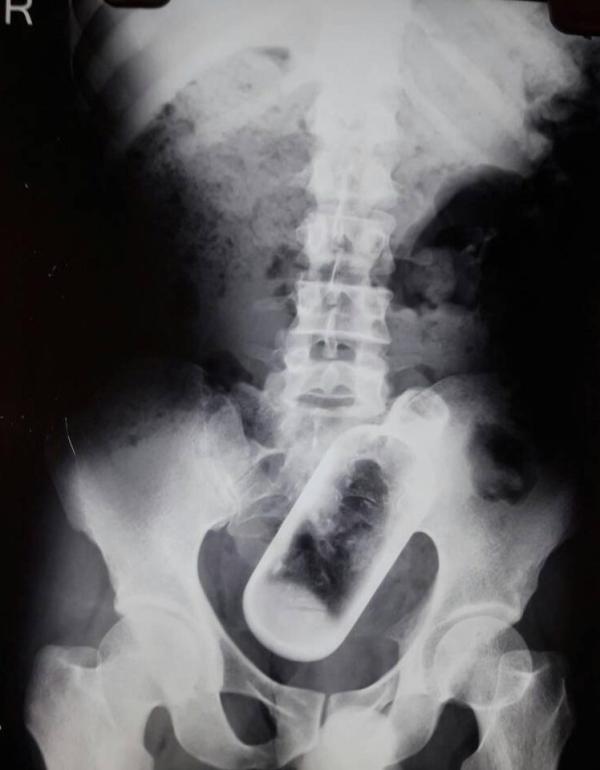

上游新闻客户端4月27日消息,据英国《太阳报》4月26日报道,印度一名36岁的男子因为时常感到胃疼去医院检查,照完X光后竟然在胶片上发现了一个神秘物体。经过进一步检查,医生在他的胯骨上方发现了一个长达16厘米的酒瓶。

图为该男子的X光胶片,在胯骨上方可以清晰地看到一个瓶子。